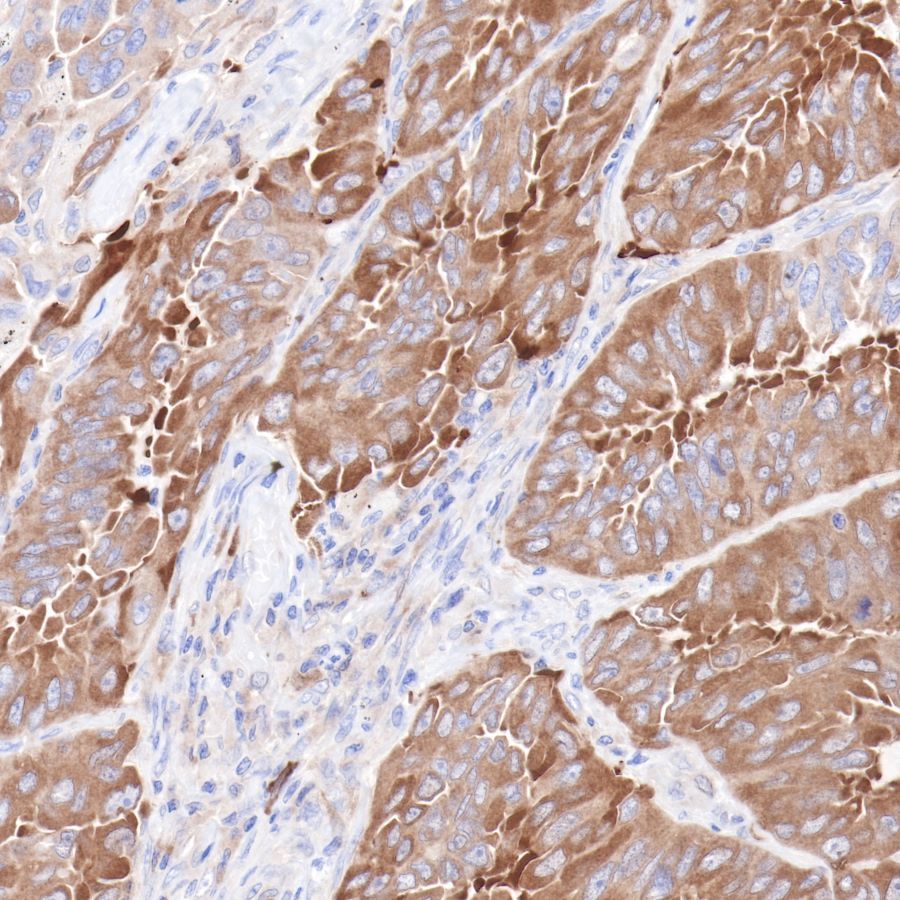

IHC shows positive staining in paraffin-embedded human lung cancer.

Anti-Hsp90 beta antibody was used at 1/2000 dilution, followed by a Goat Anti-Rabbit IgG H&L (HRP) ready to use. Counterstained with hematoxylin.

Heat mediated antigen retrieval with Tris/EDTA buffer pH9.0 was performed before commencing with IHC staining protocol.